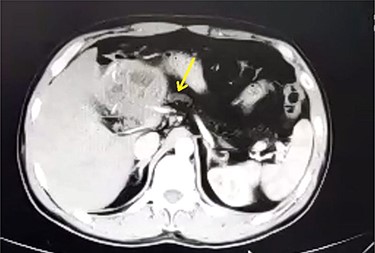

A 33-year-old male was referred to our Department of General Surgery, with a 3-month severe epigastric pain radiating to the back, associated with several episodes of green vomiting. Pain is episodic, relieved by painkillers, has no relation to food or movement. No history of changes in bowel habits or urine color. The patient reported a history of early satiety and an observed unmeasured weight loss. The past medical and surgical histories were irrelevant. Abdominal examination showed tenderness in the epigastric region, with no other signs. Laboratory tests including complete blood cell count, renal and liver function tests were within normal levels. Immunologic methods (ELISA) and indirect hemagglutination (IHA) assays were negative. Serum Amylase and CA 19-9 were within normal levels. Computed tomography (CT) scan revealed a multilocular cystic lesion in the head of the pancreas measuring 9.5 × 8.2 × 11 cm, causing external compression on the distal part of the CBD. The main pancreatic duct near the cystic mass is dilated measuring 0.5 cm. The gallbladder is distended (Figs 1 and 2).

Axial contrast-enhanced CT scan of the abdomen demonstrating a well-defined solitary cystic lesion in the head of the pancreas with a diameter of (9 cm).